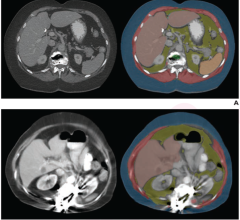

As the radiology community continues to learn and leverage the latest advancements in the use of artificial intelligence ...